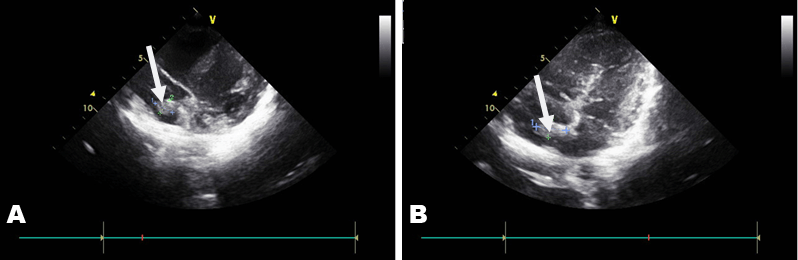

An ultrasound study of the vessels of the lower extremities revealed an intraluminal thrombus of the left superficial femoral and popliteal vein. A thoroughly detailed investigation of patient’s history revealed a minor sports related blunt injury of the left lower extremity a day before the initial symptoms, which was associated with lower extremities ultrasound findings. Additionally, an echocardiogram visualized a thrombus (2x1.5 cm) attached to the right atrium in conjunction with patent foramen ovale (Figure 5).

Figure 5 (A, B): Arrows indicate the location of the thrombus with its approximate dimensions.